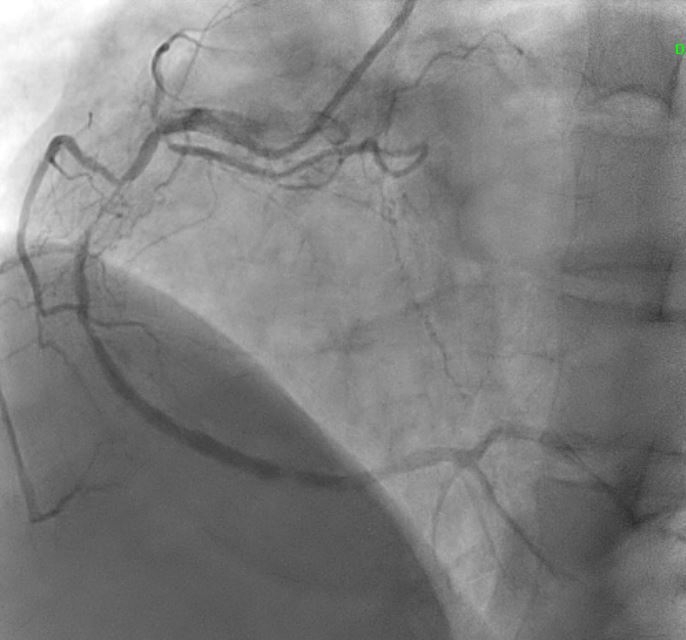

Angiographic assessment showed a normal left main stem, with severe proximal LAD disease exhibiting moderate calcification and providing retrograde collateral supply to both RCA and LCx. The LCx demonstrated severe mid-segment disease with subtotal occlusion of the obtuse marginal 1 (OM1) branch. The RCA showed severe proximal disease and total occlusion of the posterolateral(PL) branch.

Echocardiogram showed good left ventricular ejection fraction of 53%. A multislice computed tomography coronary angiogram (MSCT-Coronary) demonstrated severe stenosis involving the proximal left anterior descending (LAD),proximal left circumflex (LCx),and proximal right coronary artery(RCA).The patient was subsequently admitted electively for diagnostic coronary angiography and possible percutaneous coronary intervention (PCI).